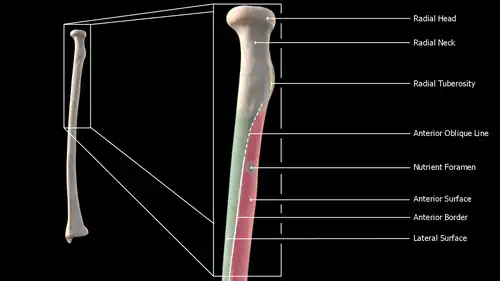

Body

The body of the radius (or shaft of radius) is prismoid in form, narrower above than below, and slightly curved, so as to be convex lateralward. It presents three borders and three surfaces.

- Borders

The volar border (margo volaris; anterior border; palmar;) extends from the lower part of the tuberosity above to the anterior part of the base of the styloid process below, and separates the volar from the lateral surface. Its upper third is prominent, and from its oblique direction has received the name of the oblique line of the radius; it gives origin to the flexor digitorum superficialis muscle (also flexor digitorum sublimis) and flexor pollicis longus muscle; the surface above the line gives insertion to part of the supinator muscle. The middle third of the volar border is indistinct and rounded. The lower fourth is prominent, and gives insertion to the pronator quadratus muscle, and attachment to the dorsal carpal ligament; it ends in a small tubercle, into which the tendon of the brachioradialis muscle is inserted.

The dorsal border (margo dorsalis; posterior border) begins above at the back of the neck, and ends below at the posterior part of the base of the styloid process; it separates the posterior from the lateral surface. is indistinct above and below, but well-marked in the middle third of the bone.

The interosseous border (internal border; crista interossea; interosseous crest;) begins above, at the back part of the tuberosity, and its upper part is rounded and indistinct; it becomes sharp and prominent as it descends, and at its lower part divides into two ridges which are continued to the anterior and posterior margins of the ulnar notch. To the posterior of the two ridges the lower part of the interosseous membrane is attached, while the triangular surface between the ridges gives insertion to part of the pronator quadratus muscle. This crest separates the volar from the dorsal surface, and gives attachment to the interosseous membrane. The connection between the two bones is actually a joint referred to as a syndesmosis joint.

- Surfaces

The volar surface (facies volaris; anterior surface) is concave in its upper three-fourths, and gives origin to the flexor pollicis longus muscle; it is broad and flat in its lower fourth, and affords insertion to the Pronator quadratus. A prominent ridge limits the insertion of the Pronator quadratus below, and between this and the inferior border is a triangular rough surface for the attachment of the volar radiocarpal ligament. At the junction of the upper and middle thirds of the volar surface is the nutrient foramen, which is directed obliquely upward.

The dorsal surface (facies dorsalis; posterior surface) is convex, and smooth in the upper third of its extent, and covered by the Supinator. Its middle third is broad, slightly concave, and gives origin to the Abductor pollicis longus above, and the extensor pollicis brevis muscle below. Its lower third is broad, convex, and covered by the tendons of the muscles which subsequently run in the grooves on the lower end of the bone.

The lateral surface (facies lateralis; external surface) is convex throughout its entire extent and is known as the convexity of the radius, curving outwards to be convex at the side. Its upper third gives insertion to the supinator muscle. About its center is a rough ridge, for the insertion of the pronator teres muscle.[3] Its lower part is narrow, and covered by the tendons of the abductor pollicis longus muscle and extensor pollicis brevis muscle.

Near the elbow

The upper extremity of the radius (or proximal extremity) presents a head, neck, and tuberosity.

- The radial head has a cylindrical form, and on its upper surface is a shallow cup or fovea for articulation with the capitulum (or capitellum) of the humerus. The circumference of the head is smooth; it is broad medially where it articulates with the radial notch of the ulna, narrow in the rest of its extent, which is embraced by the annular ligament. The deepest point in the fovea is not axi-symmetric with the long axis of the radius, creating a cam effect during pronation and supination.

- The head is supported on a round, smooth, and constricted portion called the neck, on the back of which is a slight ridge for the insertion of part of the supinator muscle.

- Beneath the neck, on the medial side, is an eminence, the radial tuberosity; its surface is divided into a posterior, rough portion, for the insertion of the tendon of the biceps brachii muscle, and an anterior, smooth portion, on which a bursa is interposed between the tendon and the bone.

Anterior view of right proximal radius

Anterior view of right proximal radius -